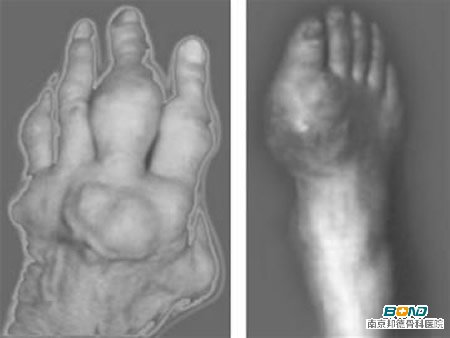

类风湿关节炎患者一旦病情发展到晚期,则可出现纤维组织增生,这是因为患病时间较长关节内滑膜受到炎症的刺激,关节软骨及骨受到侵蚀和破坏,从而出现纤维组织增生。当然还可出现关节畸形、关节强直、关节功能丧失,从而导致患者行走不便,甚至久卧在床,生活不能自理

创伤性关节炎患者如果在早期不能及时进行治疗的话,在晚期可能会表现出关节反复肿胀,疼痛持续并逐渐加重,并可出现活动受限,关节积液、畸形和关节内游离体,关节活动时出现粗糙摩擦音